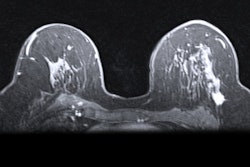

The trial will explore whether personalized risk-based screening is more efficient and safer than the National Health Service's three-year screening program. The MyPeBs (My personal breast screening) trial aims to determine whether a more customized schedule based on risk factors will result in fewer false positives and late-stage breast cancer cases.

The study will be carried out across six countries and include a total of 85,000 volunteers. Women between the ages of 50 and 70 who have never had breast cancer can sign up for the trial here.